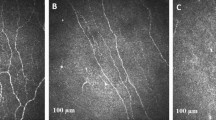

All participants underwent CCM examination using a laser scanning corneal confocal microscope HRT III (Heidelberg Retinal Tomograph III Rostock Cornea Module, Heidelberg Engineering, Heidelberg, Germany) for both eyes using our established protocol for the central and inferior whorl area of the cornea11,23. Six images from the central cornea and four images from inferior whorl at the level of sub-basal nerve plexus were selected and manually quantified using CCMetrics (The University of Manchester, Manchester, UK). Images were selected based on their quality and variability using our established protocol11,24. Four corneal parameters were quantified: corneal nerve fibre density (CNFD – total number of main nerves per square millimetre (no./mm2), corneal nerve branch density (CNBD – number of nerve branches per square millimetre), corneal nerve fibre length (CNFL – total length of main nerves and nerve branches per square millimetre) (mm/mm2), inferior whorl length (IWL – total length of nerves per square millimetre at the IW region) (mm/mm2), average nerve fibre length (ANFL) − (CNFL + IWL/2 (mm/mm2)) and total nerve fibre length (TNFL) − (CNFL + IWL (mm/mm2)).

Corneal nerve fibre density (no./mm2) (25.14 ± 0.77 vs. 36.33 ± 1.49, p < 0.0001), branch density (no./mm2) (60.14 ± 2.99 vs. 90.84 ± 7.41, P = 0.001), length (mm/mm2) (22.39 ± 0.65 vs. 26.76 ± 1.04, p = 0.001, −16.3%), inferior whorl length (mm/mm2) (22.73 ± 0.88 vs. 35.31 ± 2.11, p < 0.0001, −35.6%), average (mm/mm2) (22.56 ± 0.68 vs. 31.03 ± 1.22, P < 0.0001, −27.3%) and total (mm/mm2) (45.12 ± 1.36 vs. 62.07 ± 2.45, P < 0.0001, −27.3%) nerve fibre length were significantly lower in patients with diabetes compared to controls (Table 1). Corneal nerve fibre density (no./mm2) (26.31 ± 1.19 vs. 35.42 ± 1.6, P < 0.0001), branch density (no./mm2) (64.29 ± 5.12 vs. 89.64 ± 7.25, P = 0.004), length (mm/mm2) (23.16 ± 1.06 vs. 26.57 ± 1.45, P = 0.05, −12.8%), inferior whorl length (mm/mm2) (24.08 ± 1.4 vs. 35.18 ± 2.02, P < 0.0001, −31.6%), average (mm/mm2) (23.62 ± 1.1 vs. 30.88 ± 1.51, P < 0.0001, −23.5%) and total (mm/mm2) (47.24 ± 2.21 vs. 61.75 ± 3.02, P < 0.0001, −23.5%) nerve fibre length were significantly lower in DN− compared to controls, after adjustment for age. Corneal nerve fibre density (no./mm2) (24.5 ± 0.9 vs. 35.42 ± 1.6, P < 0.0001), branch density (no./mm2) (56.94 ± 4.11 vs. 89.64 ± 7.25, P < 0.0001), length (mm/mm2) (21.84 ± 0.87 vs. 26.57 ± 1.45, P = 0.007, −17.8%), inferior whorl length (mm/mm2) (21.56 ± 1.2 vs. 35.18 ± 2.02, P < 0.0001, −38.7%), average (mm/mm2) (21.70 ± 0.9 vs. 30.88 ± 1.51, P < 0.0001, −29.7%) and total (mm/mm2) (43.4 ± 1.8 vs. 61.75 ± 3.02, P < 0.0001, −29.7%) nerve fibre length were significantly reduced in patients with DN+ compared to controls, after adjustment for age (Figs 1 and 2). There was no significant difference in any CCM parameter between diabetic patients with and without DPN (Table 2).